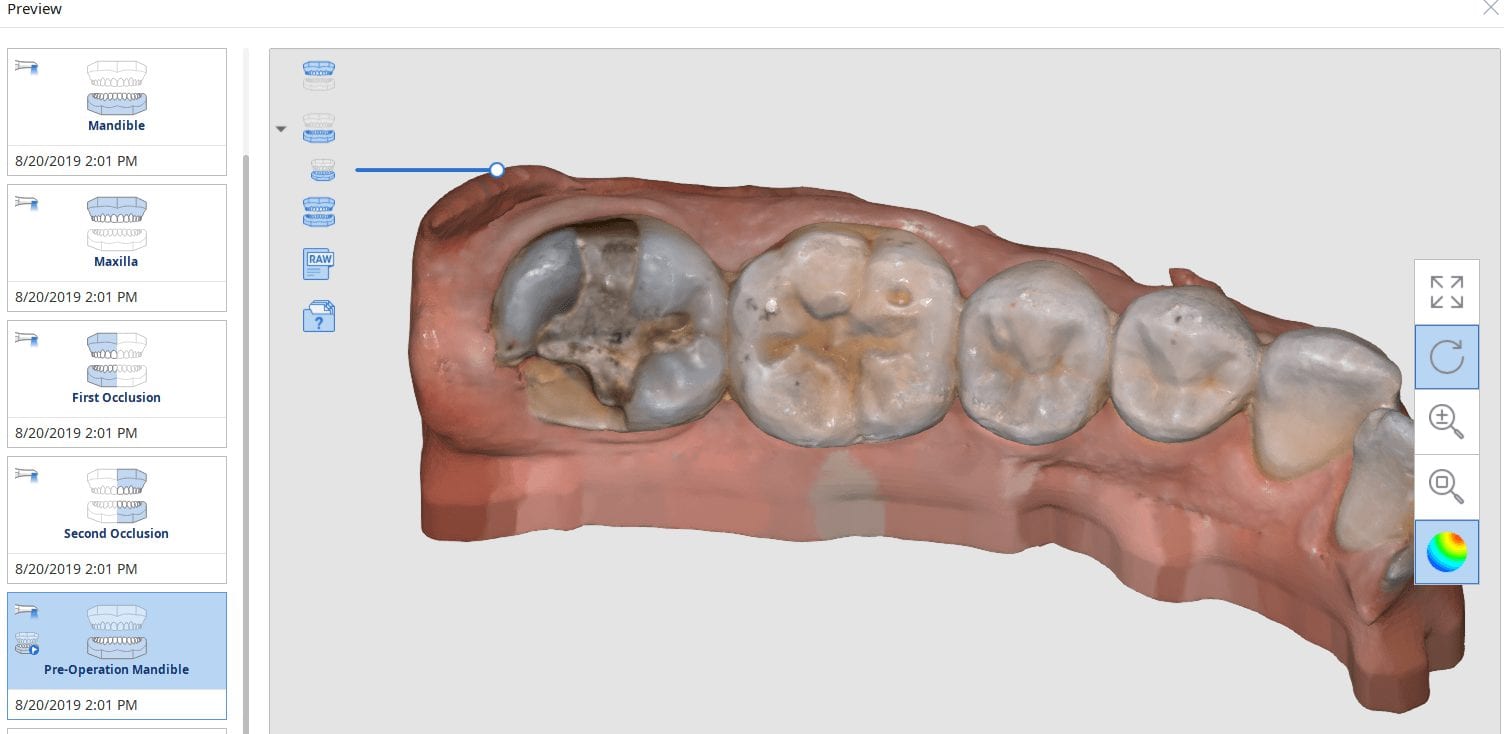

August 22, 2019A new feature coming to Medit i500 is the automatic detection of scanbodies while you are imaging. In this clinical case, two implants are placed in the lower left quadrant […]